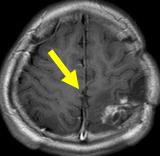

文字方塊: 每年磁共振造影追蹤動靜脈畸形可見逐年消失

文字方塊: 2005.02.23

文字方塊: 病患A 14歲 男性

診斷:動靜脈畸形